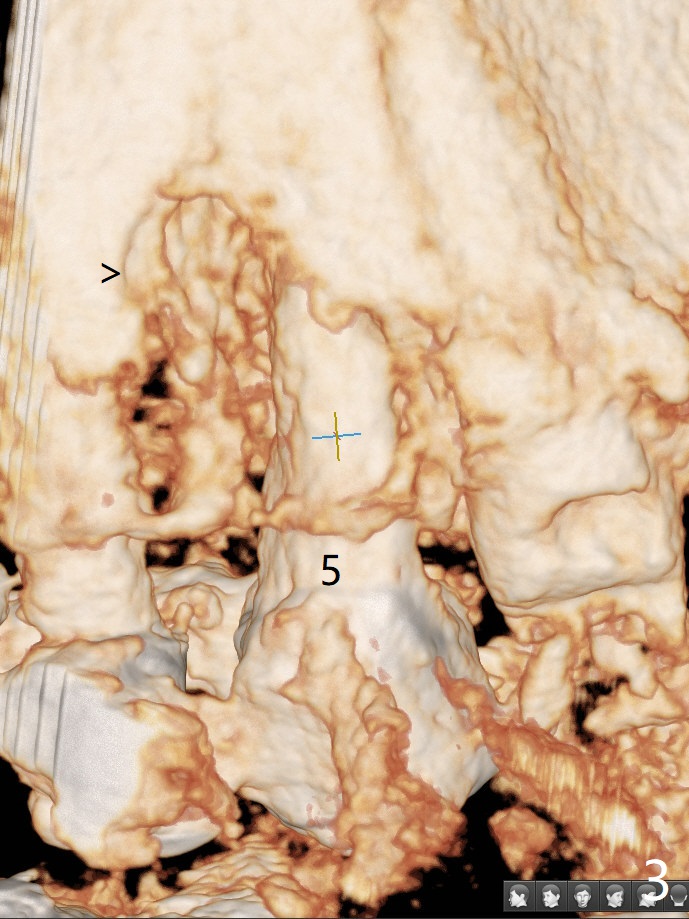

A 90-year-old man (bruxer) has porcelain fracture at #4. PA happens to reveal large PARL at #5 (Fig.1). CT taken a year ago shows missing buccal canal (Fig.2). Bone loss seems to be extensive (Fig.3,4 (root fracture?)). Access to the canal through PFM fails; the crown has to be removed (Fig.5). Fortunately the buccal canal is found and negotiable.